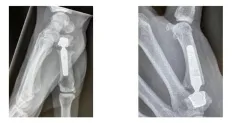

Este martes 20 de abril, los especialistas en Ciriugía Ortopédica y Traumatológica, el Dr. Borrego y el Dr. Pajares realizarán una artroplastia del pulgar utilizando las nuevas prótesis trapeciometacarpianas de doble movilidad.

El Dr. Samuel Pajares de la Clínica Universidad de Navarra y el Dr. David Borrego de la FHGST son los encargados de iniciar este ciclo de sesiones con una artroplastia de la articulación trapecio metacarpiano, una de las cirugías ortopédicas más realizadas, ya que afecta a la mayoría de las mujeres de mediana edad, con un efecto muy negativo en su calidad de vida por la pérdida de fuerza y el dolor asociado.

La artroplastia de la articulación trapecio metacarpiano es una intervención ambulatoria cada vez más demandada, en la que paciente recibe el alta el mismo día y cuyo tiempo de recuperación es menor. A los tres o cuatro días después de la intervención se puede empezar la rehabilitación.